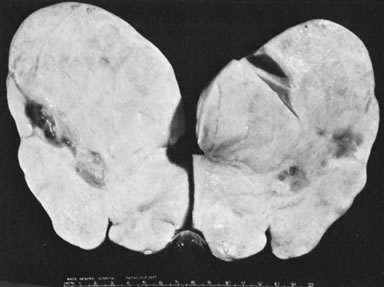

In 10% to 15% of the cases, the granulosa cell tumor does not cause palpable ovarian enlargement, and unless ultrasound examination is performed before surgery, is not detected until the time of a hysterectomy for another indication, such as atypical endometrial hyperplasia or carcinoma. More often, the tumor is palpable on pelvic or abdominal examination. At operation, it may appear solid or have both solid and cystic components (Fig. 1). On sectioning, the solid tissue may be gray, white, or yellow, reflecting the amount of intracellular fat it contains, and may be soft or firm depending on the relative quantities of granulosa cells and fibrothecomatous components. Two types of gross presentation are highly suggestive of granulosa cell tumor. One is a solid, pale yellow mass associated with extensive hemorrhage, and the other is a multicystic tumor with the locules filled with fluid or clotted blood. A rare appearance is that of a large unilocular or oligolocular thin-walled cystic tumor, resembling a serous cystadenoma; curiously, this gross appearance unusually often is associated with virilization instead of estrogenic changes.6 In summary, the granulosa cell tumor can simulate a variety of other types of ovarian tumor on gross examination, but the diagnosis may be suggested by the gross features, particularly in some clinical settings.

Fig. 1. Sectioned surface of granulosa cell tumor with solid and cystic components.(Scully RE: Ovarian tumors with estrogenic manifestations. Contemp Ob Gyn 10:83, 1977.)